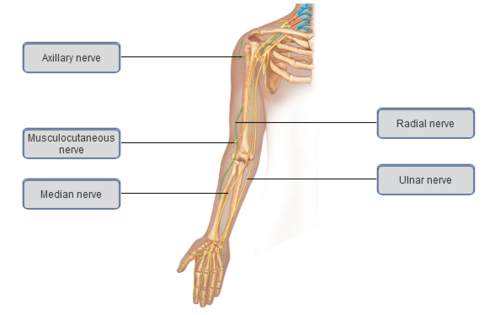

Brachial plexus and peripheral nerves

Axillary nerve

Musculocutaneous nerve

Median nerve

Radial nerve

Ulna nerve

C5 – T1